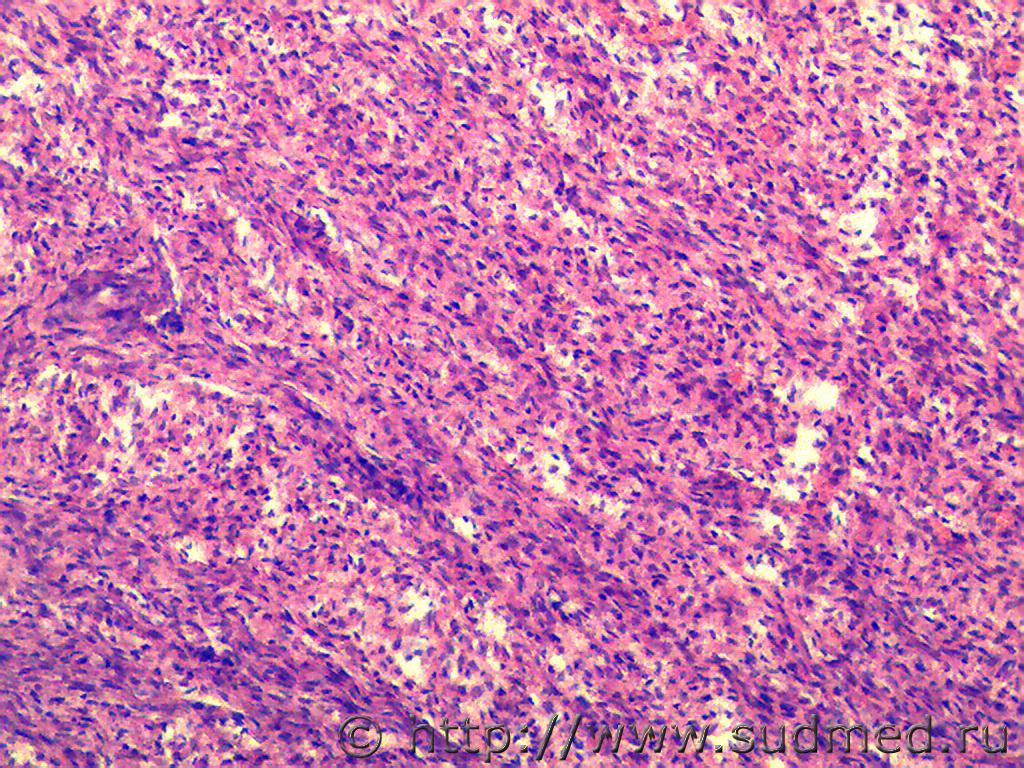

Первые две: ганглионеврома надпочечника (гистологич.находка, случай ДТП)

Вторые две: пневмоцистная пневмония, ГЭ, по Grocott не красим